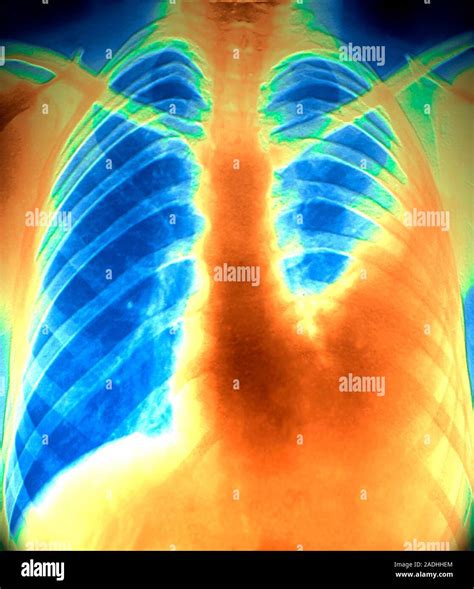

Lung Embolism X Ray

Lung embolism is a serious medical condition that occurs when a blood clot, fat, air, or other substances block the pulmonary arteries, which carry blood from the heart to the lungs. This blockage can lead to severe complications, including shortness of breath, chest pain, and even death if not treated promptly. One of the critical diagnostic tools used to identify a lung embolism is the Lung Embolism X Ray. This imaging technique plays a pivotal role in the early detection and management of this life-threatening condition.

When a lung embolism is suspected, a Lung Embolism X Ray may reveal:

• Enlarged pulmonary arteries

• Pleural effusion (fluid around the lungs)

• Atelectasis (collapse of lung tissue)

• Pneumonia or other lung infections

However, these findings are not specific to a lung embolism and can be seen in other conditions as well. Therefore, additional diagnostic tests, such as a CT scan or a ventilation/perfusion (V/Q) scan, are often required to confirm the diagnosis.